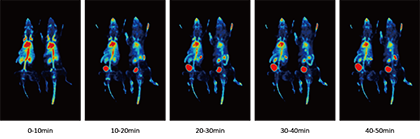

4、动态成像技术

同步实现药物注射和数据采集。实时跟踪示踪剂在动物体内的动态分布,精确分析药物的代谢过程。